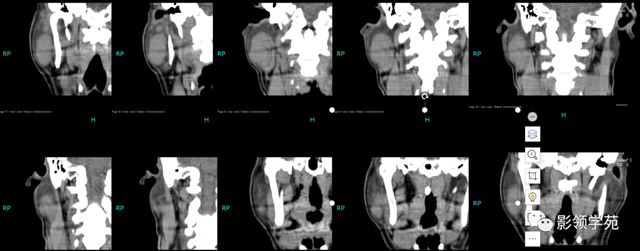

【影像体现】:右侧腮腺不规则增大,边缘强化不规则,CT值为15-44HU,内有低密度坏死区,且见脱离 ,周围显着 强化,未见肿大淋投合。

【影像诊断】:右腮腺脓肿。

2.腮腺脓肿:体现为腮腺局限性肿块并黑点状坏死,典型者可见环状强化,伴相近 筋膜增厚和皮下脂肪层模糊,团结 临床局部皮温升高可诊断。